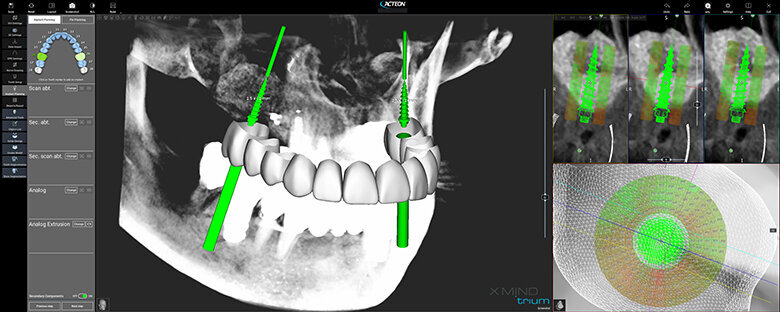

Figure 1 shows a split-mouth case with a bilateral INTRALIFT procedure: after a small crestal “booklet”-flap of approx. 7x7mm is detached, the sinus floor is safely opened with ultrasound Piezotome tips (Figs. 2 & 3), the sinus membrane then detached by the hydrodynamic cavitation effect of the Piezotome-tip TKW5 plugged into the approach canal (Figs. 4 & 5) and the subantral scaffold filled with 2cm of randomly assigned biomaterial (Figs. 6 & 7), followed by wound closure (Fig. 8). After a mean healing period of 8,4 months X-Mind trium CBCT scans were performed, the digital setup of the future bridge constructed with the AIS 3D app and the bone density determined in the sinus-lift site around a virtual implant (Fig. 9). Standardised implants (4mm in diameter and 12mm in length) were then inserted in the position of the virtual implant and insertion torque values (ITV) measured intra-surgically (test groups; Fig. 10). A total of 27 patients with sufficient native subantral crestal bone (min. crest width: 6 mm, height: 12 mm) were screened by X-Mind trium CBCT for bone density with the virtual implant (Fig. 11), the standardised implant inserted and the ITV recorded (control group). Figure 12 depicts the final result after implant insertion in the patient case shown in Figures 1–9.

As can be seen in Fig. 13, the mean CBCT bone density values in Hounsfield units (HU) at the implant site differed significantly (p <0.05) between all four test groups and the control group. The precise numerical HU values are “translated” by AIS 3D app software and are also colour-coded for easier interpretation at first glance: the brighter the green the CBCT voxel matrix shows around the virtual implant, the higher the bone density, with a virtual neutral threshold of 500 HU. Contrary, the more reddish the CBCT voxel matrix around the digital implant is depicted, the worse the biomechanical bone quality (Fig. 14). The corresponding insertion torque values (ITV) of the inserted standardised implant measured at the location of the transcrestal INTRALIFT approach (Fig. 2) also differed significantly between all test groups and the control group. Figure 15 depicts the cumulative result of the correlation between HU and ITV values for all test groups and the control group.

As the presented study proves, contemporary CBCT technology adds another outstanding feature to the general CBCT-based digital workflow as the first and only tool to safely determine the grade of primary implant stability to be expected at each individual implant site already in the planning phase before the treatment or surgery is performed (Fig. 16). By using CBCT-based bone densitometry as an integrated diagnostic step in the digital workflow, the clinician for the first time can decide individually for each patient and each implant site whether an implant insertion with immediate prosthetic loading might bear an unacceptable risk of early or delayed implant loss, and can therefore inform the patient accordingly based on evidence.